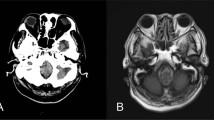

An MRI scan (signa 1.5 T) of the brain and whole spinal cord was undertaken within 24 h of the injury, which failed to show any abnormalities. MRI was again repeated 3 weeks after the injury. This showed an area of abnormal high signal within the posterior aspect of the cord from C3 level down to C4/5 disc space (Figure 1). The MRI brain revealed an area of high signal lying high within the left cerebral hemisphere just supero-lateral to the left ventricle (Figure 2).

An initial MRI scan of the brain obtained 3 days after the accident revealed an abnormally high signal in the white matter (Figure 3). This had resolved on repeat MRI performed 8 weeks after the injury. Also, an MRI of the cervical spine performed 3 days after the accident showed an abnormally high signal at C3–4 level (Figure 4), which then disappeared on repeat scan 10 weeks later.

Both patients developed higher cerebral function impairment (Encephalopathy) early on during the course of their illness manifested by loss of consciousness, which indicates bilateral cerebral dysfunction or brain stem (reticular activating system) involvement. Interestingly, MRI scan of the first patient within the first 24 h failed to show any abnormality, however, repeat scans 3 weeks later did reveal abnormally high signals in both the brain and the spinal cord. The second patient had MRI scans 3 days after the injury and did show abnormally high signal in both the brain and the spinal cord.